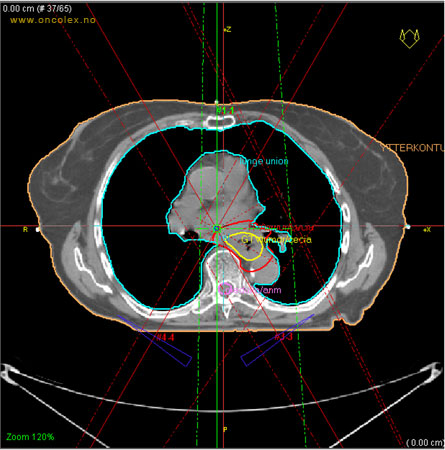

Skisse over hvordan strålefeltet planlegges:

Illustrasjon for målvolum

• GTV (Gross Tumor Volume): Identifisert tumor.

• CTV (Clinical Target Volume) GTV + omkringliggende vev hvor det kan væremikroskopisk spredning.

• ITV (Internal Target Volume): CTV + en indre margin som tar hensyn tilindre bevegelser og endringer av CTV.

• PTV (Planning Target Volume): Innstillingsmargin som inneholder ITV og samtidig tar hensyn til antatte pasientbevegelser, samt variasjoner i pasientopplegging og feltinnstillinger.

• Feltgrense. Tegnes som oftest på kroppen.

ICRU (International Commission on Radiation Units and Measurements)